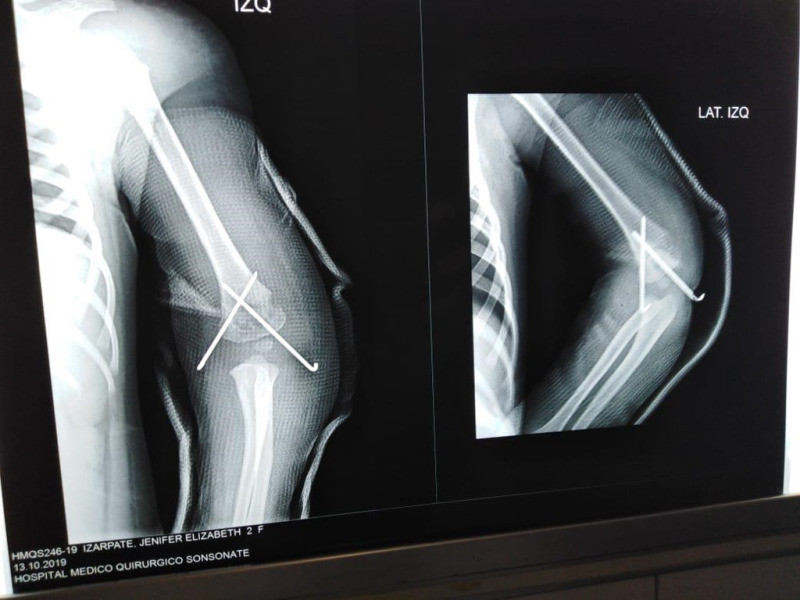

Imágenes de ortopedia y traumatología

Envíado por Dr. José Israel Flores Hernández